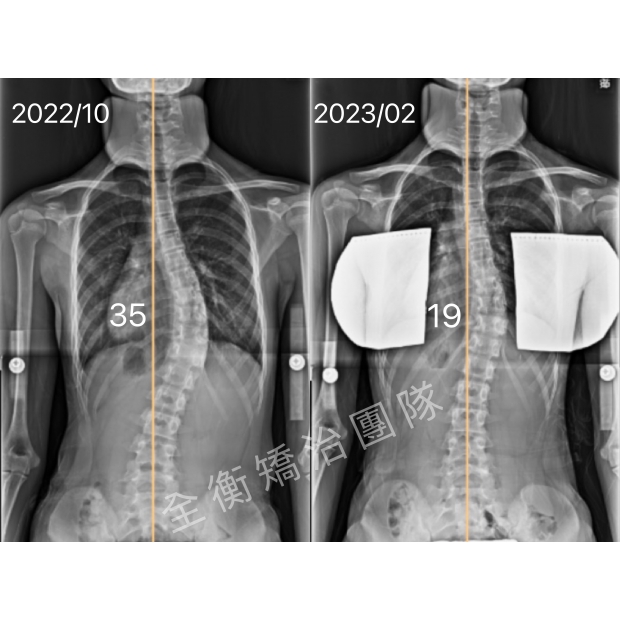

12嵗側彎女生,4個月,大C變小C12嵗側彎女生,4個月,大C變小C

這位12歲妹妹,小五時發現胸彎15度

來我們診所初診時已經惡化至35度

並伴隨15度的旋轉,背部右側隆起明顯

透過「德國施羅斯療法」的運動治療和背架矯正

4個月時間減少了16度,從大胸彎變成小胸彎 -